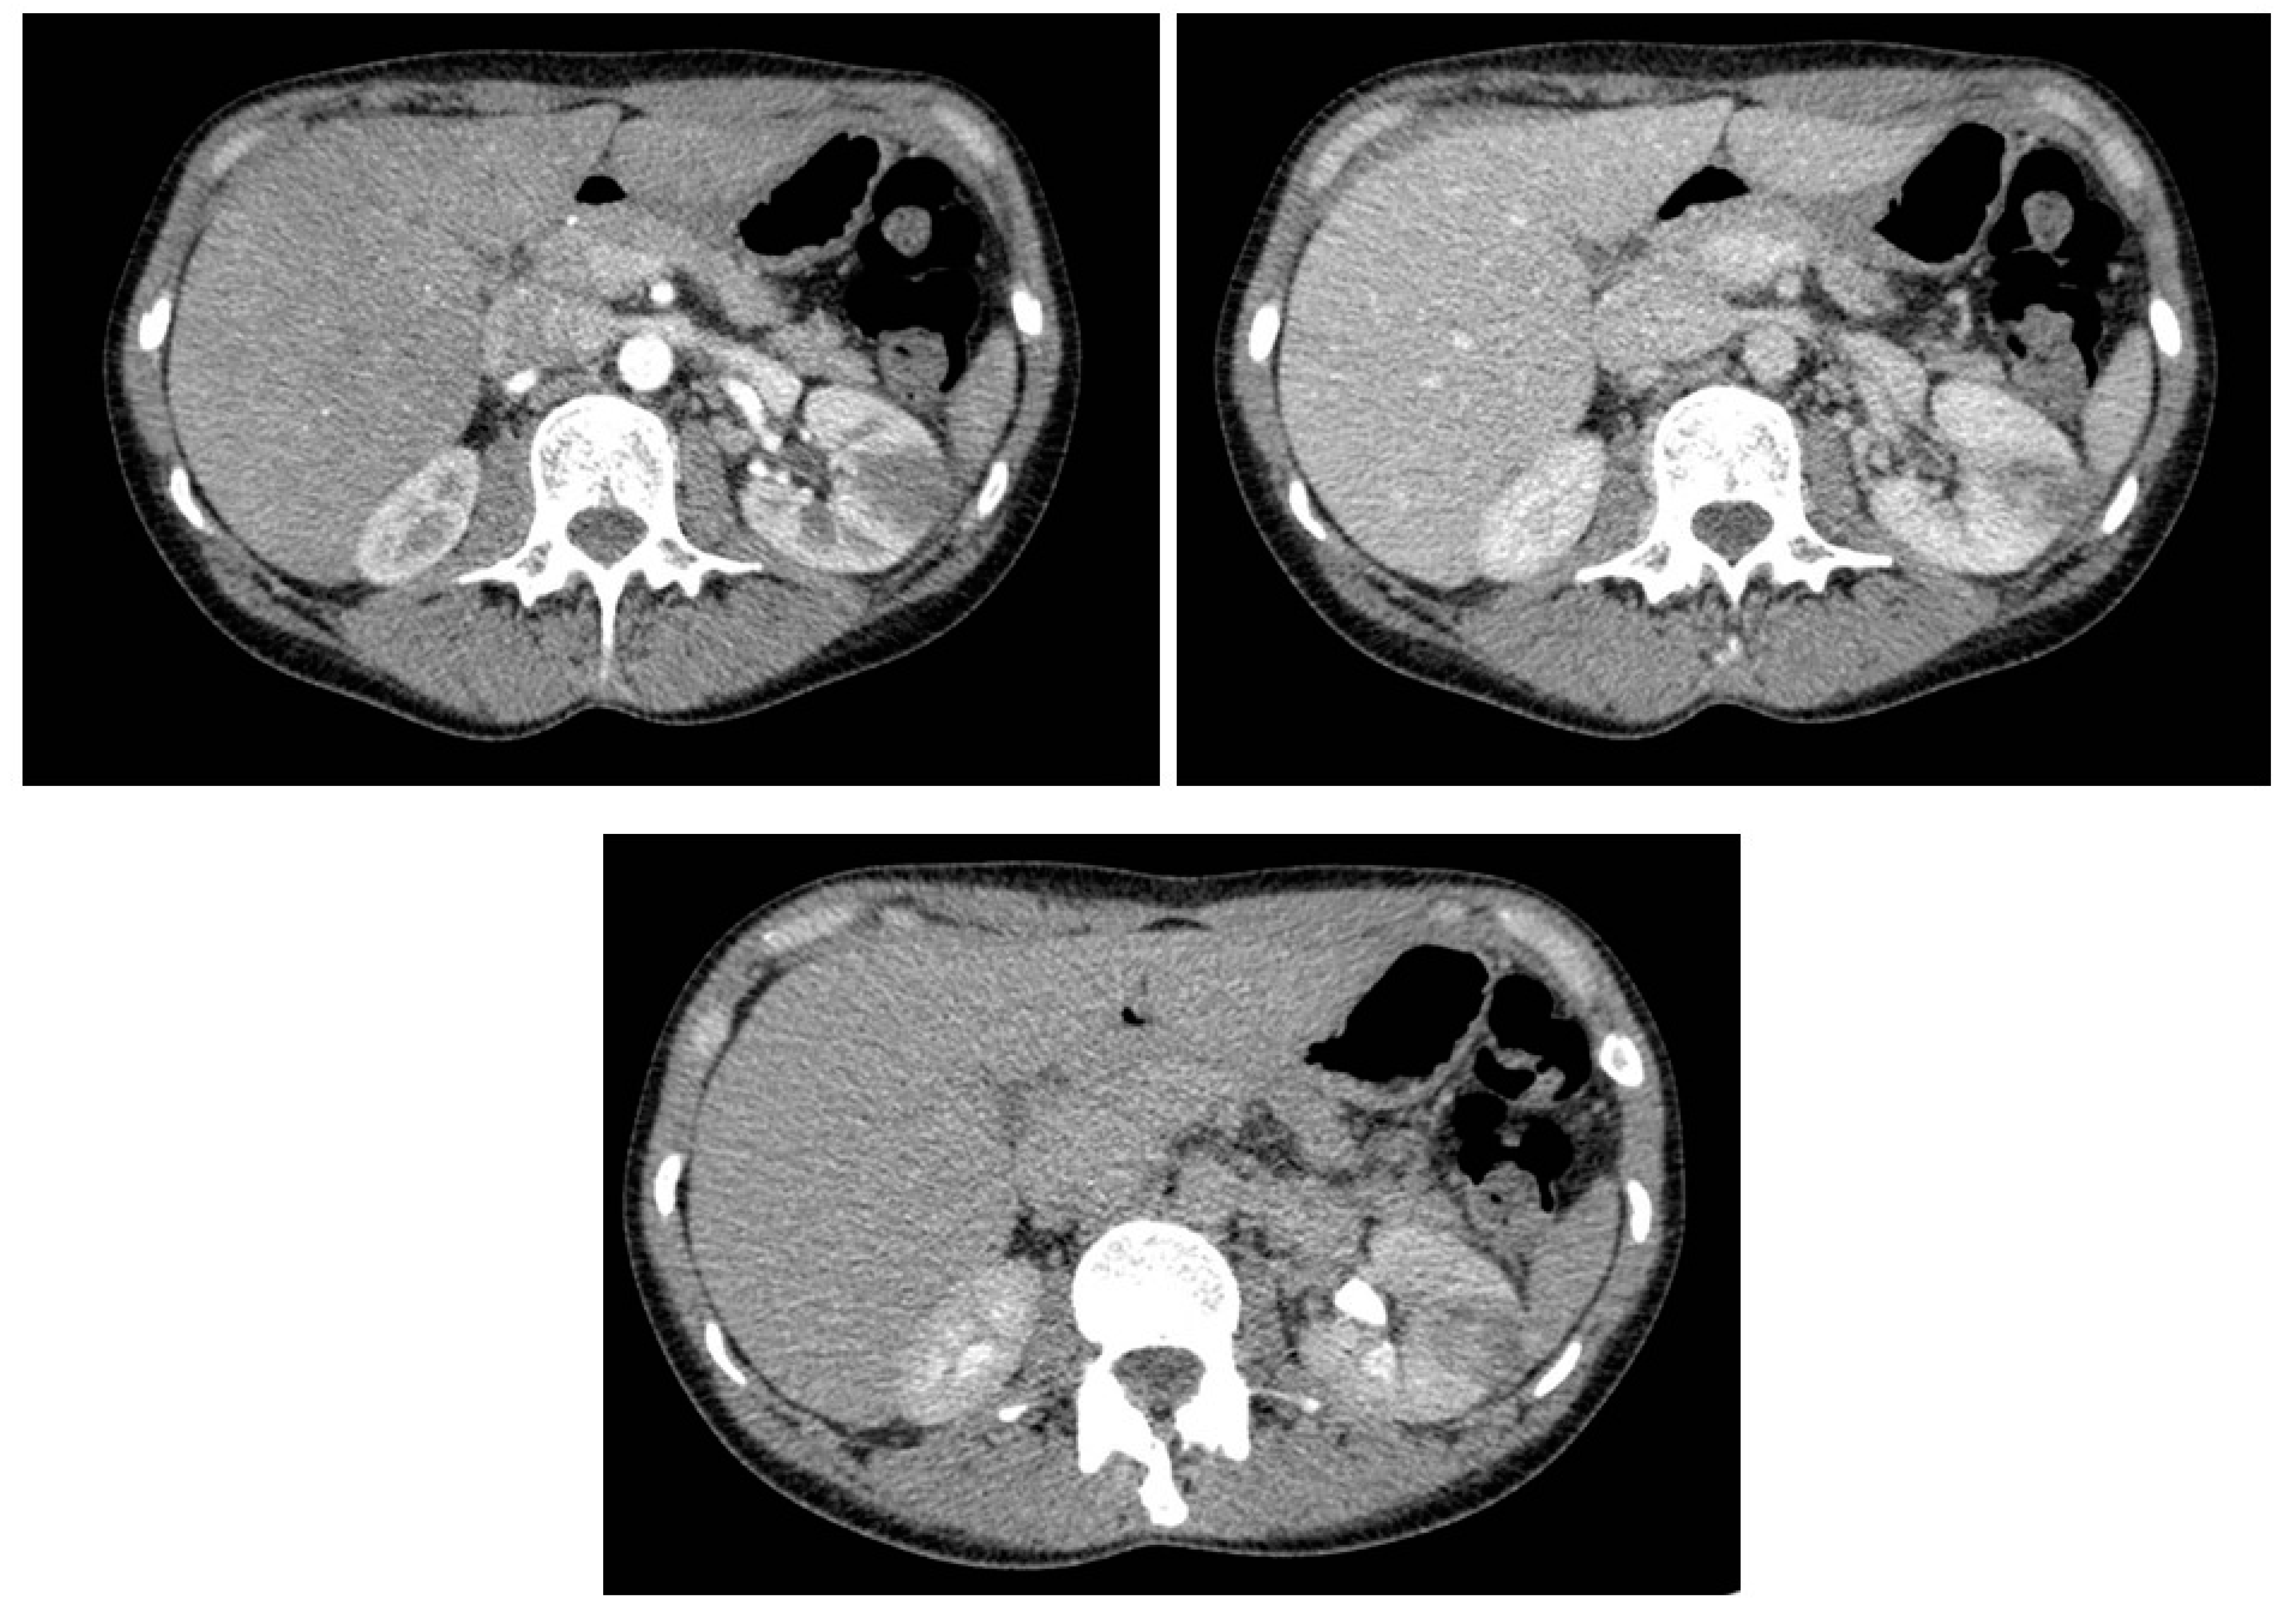

3. Results